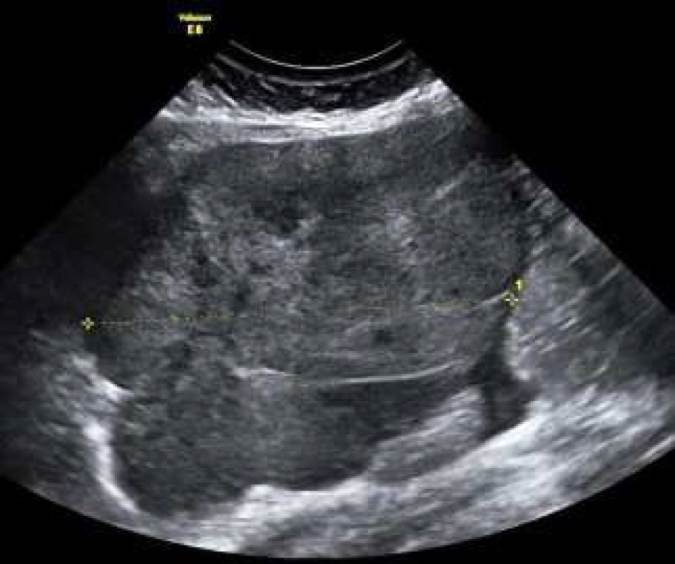

Det är relativt vanligt förekommande med metastaser i ovarierna från andra maligna tumörer, vanligast förekommande är metastaser från kolorektal, övre GI, ventrikel, lymfom och bröstcancer. Det finns studier som har visat att metastaser från lymfom, bröst-, och ventrikelcancer ofta är solida medan metastaser från colorektal, gallblåse, pancreascancer ofta är flerrummigasolida med inslag av nekros 10,11 (Bild 9-12). Vid spridd bukmalignitet kan vara svårt att tala skilja primär ovarialcancer från metastaserade cancer av annan genes, inslag av tumörnekros, avsaknad av ovarialtumör talar dock för icke ovariell genes. Transvaginal eller transabdominell mellanålsbiopsi är en snabb enkel minimal-invasiv metod att fastställa tumörens primaritet.

Bild 9. Coloncancermetastas hos 19 årig kvinna i HNPCC familj.

Bild 10. "Krukenberg tumör", ventrikelcancermetastas

Bild 11. Flerrummig solid pancreascancer metastas.

Bild 12. Solid bröstcancer metastas